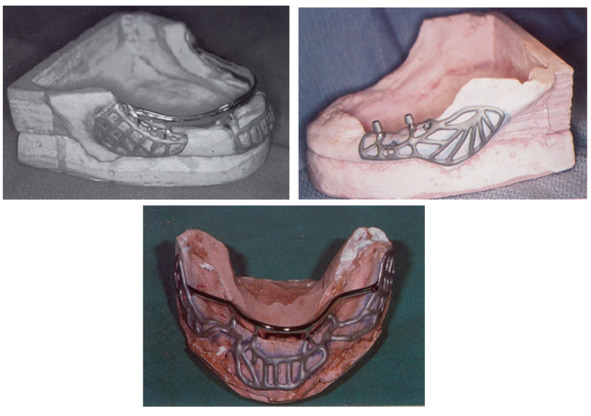

- Поднадкостничные имплантаты

- Имплантат Ramus-frame